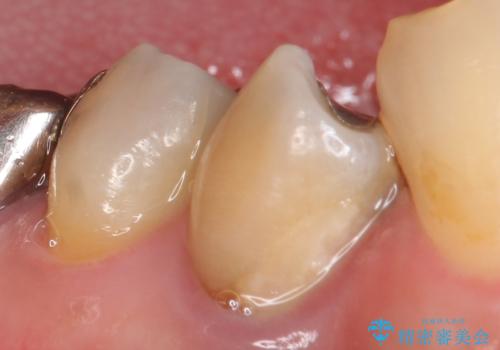

再根管治療終了後、オールセラミッククラウンによる補綴を行いました。

今回用いたオールセラミッククラウンは、ジルコニアフレームという白い素材の上にセラミックを盛っているため審美性が非常に高いのが特徴です。

またジルコニアは人工ダイヤモンドの材料にも使われているほど高い強度を持っており、そのためオールセラミッククラウンは審美性だけでなく、奥歯やブリッジの補綴も可能とするクラウンです。